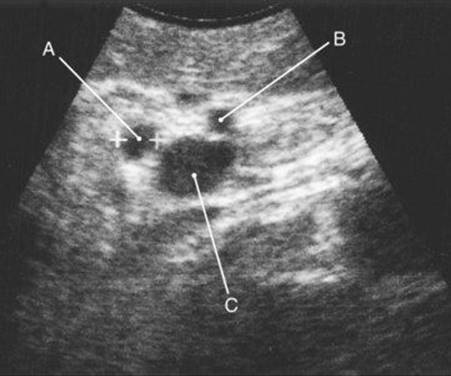

5 In this longitudinal laparoscopic ultrasound scan of the hepatoduodenal ligament, what structure is labeled B?

image

Comments

See Question 6.

6 In this transverse laparoscopic ultrasound scan of the hepatoduodenal ligament, which structure is labeled B?

A general principle of ultrasonography is that any structure visualized in one plane should also be examined in a second plane at a 90-degree angle to the first view to ascertain where and what the structure is. Intraoperative ultrasound imaging, whether laparoscopic or open, is an accurate method for identifying bile duct anatomy and assessing the bile duct for stones during cholecystectomy. The longitudinal and transverse scans of the hepatoduodenal ligament in Questions 5 and 6 depict typical anatomy. In the longitudinal plane, the common bile duct appears as a hypoechoic, tubular structure parallel and anterior to the portal vein. The normal upper-limit diameter of the duct at this location is 6 mm by ultrasound imaging criteria. In other words, a nondilated duct should not exceed one half the diameter of the neighboring portal vein. The right hepatic artery most commonly crosses behind the bile duct and is viewed in cross section on the longitudinal scan. In the transverse plane, the structures of the hepatoduodenal ligament have a “Mickey Mouse” configuration. The cross sections of the bile duct and common hepatic artery appear as smaller hypoechoic circles anterior to the larger portal vein. The structures labeled in the scan from Question 5 are as follows: A, liver; B, common bile duct; C, right hepatic artery; D, portal vein. The structures labeled in the scan from Question 6 are as follows: A, common bile duct; B, common hepatic artery, C, portal vein.